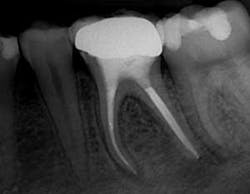

Fig. 1. Post-op radiograph showing severe curvatures of the thin mesial root and the very conservative shape cut by GT Series X Files.

Obturation was accomplished with the continuous wave obturation technique. Final radiographs revealed mesial canals with severe curvatures filled with no evidence of apical transportation with an isthmus canal as large as a primary canal cleaned and filled, and an apical bifurcation of the MB canal. The distal canals were apically confluent, and obturated with remarkable accuracy considering the large apical canal diameters.